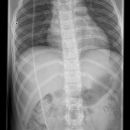

Shuntverlauf

Technik

FDA: 1,15 m

Ausgangsformat: je nach Körperregion

mit Raster

Indikation

Shuntkontrolle

Lagerung

1. Schädel/HWS ap

Patient in Rückenlage, Kinn anziehen lassen, 15° Keil unter den Kopf, so dass Deutsche Horizontale (DH = Frankfurter) senkrecht zum Film steht, Kopf muss seitengleich, symmetrisch gelagert werden.

2. Schädel/HWS seitlich

Patient in Rückenlage, Kopf auf die rechte Seite drehen und Medianebene verläuft parallel zum Tisch, Stirn-Augenbrauen-Linie verläuft senkrecht und die Stirn-Kinn-Punkte verlaufen parallel zur Filmeinblendung. Der Körper dreht sich somit etwas auf die rechte Seite.

3. Thorax/Abdomen

Patient in Rückenlage, Arme am Körper entlang, Beine geschlossen.

4. evtl Becken

Patient in Rückenlage, Beine leicht gespreizt.

Zentralstrahl

Senkrecht auf Objekt, vom Schädel bis Abdomen müssen alle Bilder überlappend sein.

Variante

Abdomen evtl seitlich röntgen, wenn die Shuntlänge 3-4cm unterhalb der Markierung ist (nicht mehr im kleinen Becken) -> Belichtung dann wie seitliche Wirbelsäule.

Anmerkung

Die Stelle (Narbe) an der der Shunt in dem Abdomen verschwindet, muss mit einer Metallkugel etc. markiert werden.